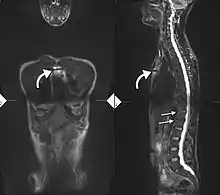

34-year-old male with AS. Inflammatory lesions of the anterior chest wall are shown (curved arrows). Inflammatory changes are seen in the lower thoracic spine and L1 (arrows).

Ankylosing spondylitis is a member of the more broadly defined disease axial spondyloarthritis.[21][22] Axial spondyloarthritis can be divided into two categories: radiographic axial spondyloarthritis (which is a synonym for ankylosing spondylitis) and non-radiographic axial spondyloarthritis (which include less severe forms and early stages of ankylosing spondylitis).[21]

While AS can be diagnosed through the description of radiological changes in the sacroiliac joints and spine, there are currently no direct tests (blood or imaging) to unambiguously diagnose early forms of ankylosing spondylitis (non-radiographic axial spondyloarthritis). Diagnosis of non-radiologic axial spondyloarthritis is therefore more difficult and is based on the presence of several typical disease features.[21][23]

If these criteria still do not give a compelling diagnosis magnetic resonance imaging (MRI) may be useful.[21][23] MRI can show inflammation of the sacroiliac joint.